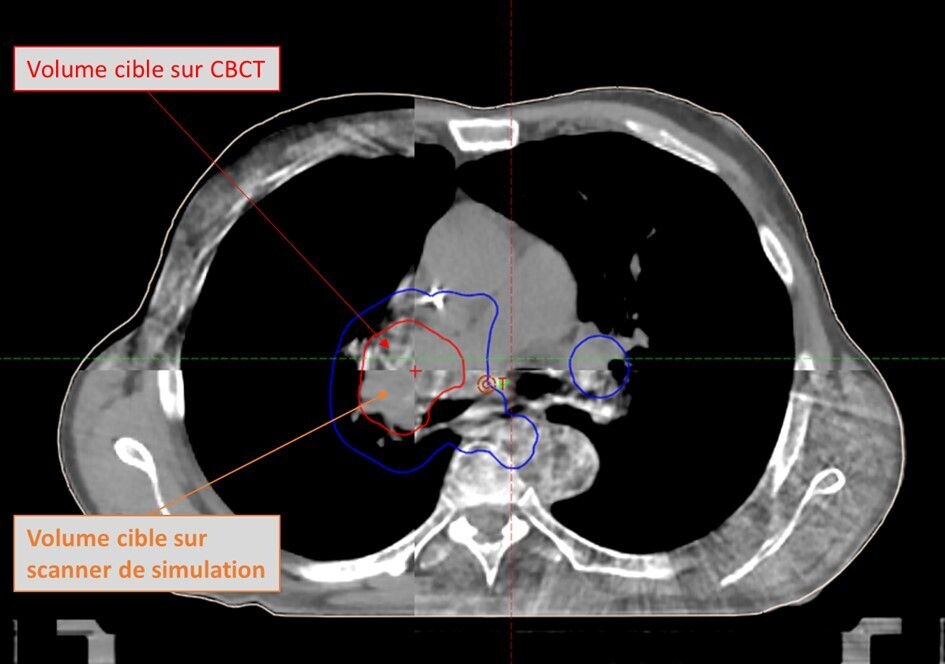

Parmi ces avancées, la tomographie par faisceau conique (CBCT  : Cone beam computed tomography) joue un rôle central en réduisant les marges entre le volume cible clinique (CTV) et le volume cible planifié (PTV).1 Cette réduction des marges permet de diminuer la dose au niveau des tissus sains tout en assurant une couverture optimale de la tumeur. Historiquement, la qualité d’image des CBCT classiques était inférieure à celle des scanners pour la planification. Cette limite entravait une délinéation précise des tumeurs et des tissus sains ainsi qu’un calcul optimal des doses. Les technologies CBCT de nouvelle génération (figure) ont considérablement amélioré la ­qualité d’image en matière de résolution spatiale, de réduction des artefacts et de précision des calculs de dose, rendant ces systèmes désormais adaptés à la personnalisation quotidienne des traitements.15